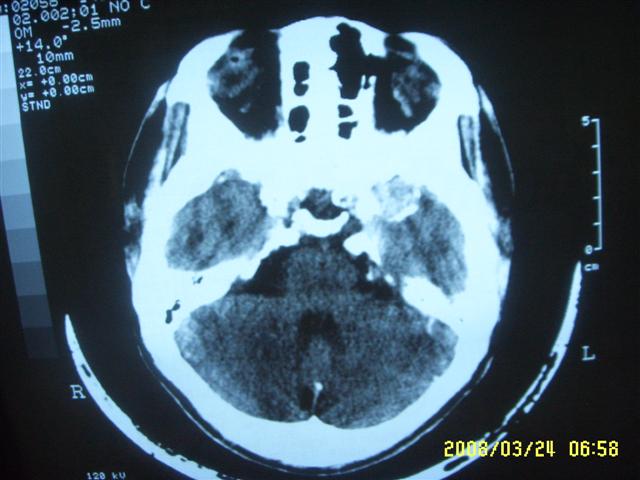

以下是引用dyqct在2008-4-2 20:09:00的发言:[br]考虑为:神经纤维瘤病(nf1型)。建议增强进一步检查。